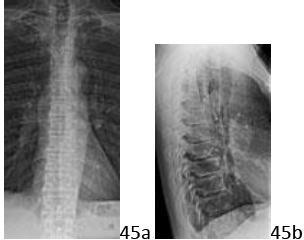

7. # 45a 45b An otherwise healthy 68-year-old man has thoracic pain with radiation along his chest wall. His pain began a few weeks ago and is constant. He denies any neurologic symptoms. AP and lateral thoracic radiographs are shown in Figures 45a and 45b. What is the next most appropriate step in management?

DISCUSSION: The next most appropriate step in management should be to obtain an MRI scan because the AP image has a missing pedicle on the left side in the upper thoracic spine; this is known as a "winking owl" sign and is the result of pedicle destruction from neoplastic disease,

most commonly metastatic in this age group. Although physical therapy and observation can be the initial management for a few weeks of pain, this radiographic finding warrants immediate further imaging. Infection more commonly destroys the disk and works its way into the vertebral body; in this patient the disks are well preserved as seen in Figure 45c. The Preferred Response to Question # 45 is 5.